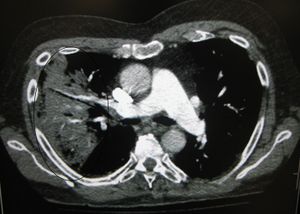

CT of the chest demonstrating right sided pneumonia (left side of the image).